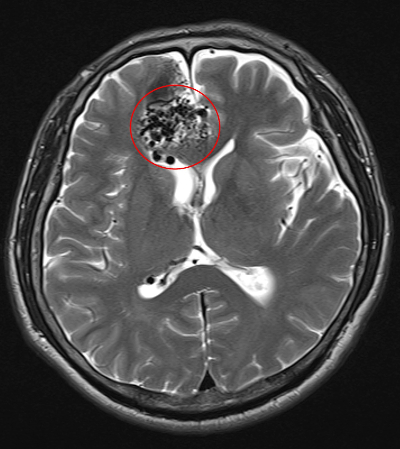

뇌 동정맥 기형(AVM)은 뇌의 동맥과 정맥이 비정상적으로 연결되어 혈류의 이상을 초래하는 선천성 질환입니다. 이러한 기형은 뇌출혈의 주요 원인 중 하나로, 조기에 발견하고 적절한 치료를 받지 않으면 심각한 신경학적 손상이나 생명 위협을 초래할 수 있습니다. 건강보험공단에서는 이러한 중증 뇌혈관질환 환자들을 위해 산정특례 제도를 통해 의료비 부담을 경감할 수 있는 혜택을 제공하고 있습니다. 이번 글에서는 뇌 동정맥 기형으로 인한 뇌출혈, 수술적 치료 방법, 그리고 산정특례 제도의 적용에 대해 자세히 알아보겠습니다.

뇌 동정맥 기형은 혈관벽이 약해져 있어 출혈의 위험이 높습니다. 특히, 다음과 같은 증상이 나타날 수 있습니다: